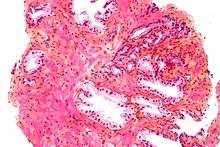

Histology

- Glandular cells

- Myoepithelial cells

- Subepithelial interstitial cells[17]

Microscopic glands of the prostate